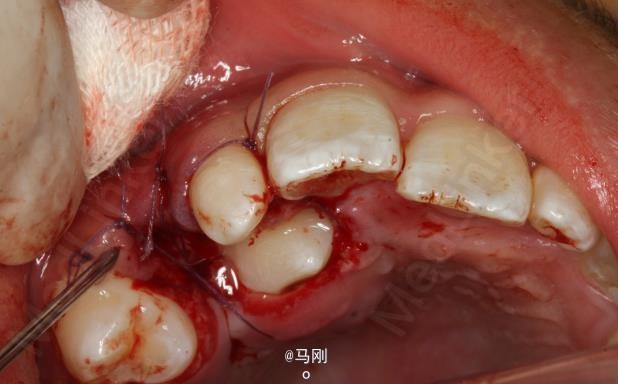

诊断 处理

处理:建议拔除右侧乳尖牙,并外科开窗牵引导萌13。患者同意治疗方案。签知情同意书。